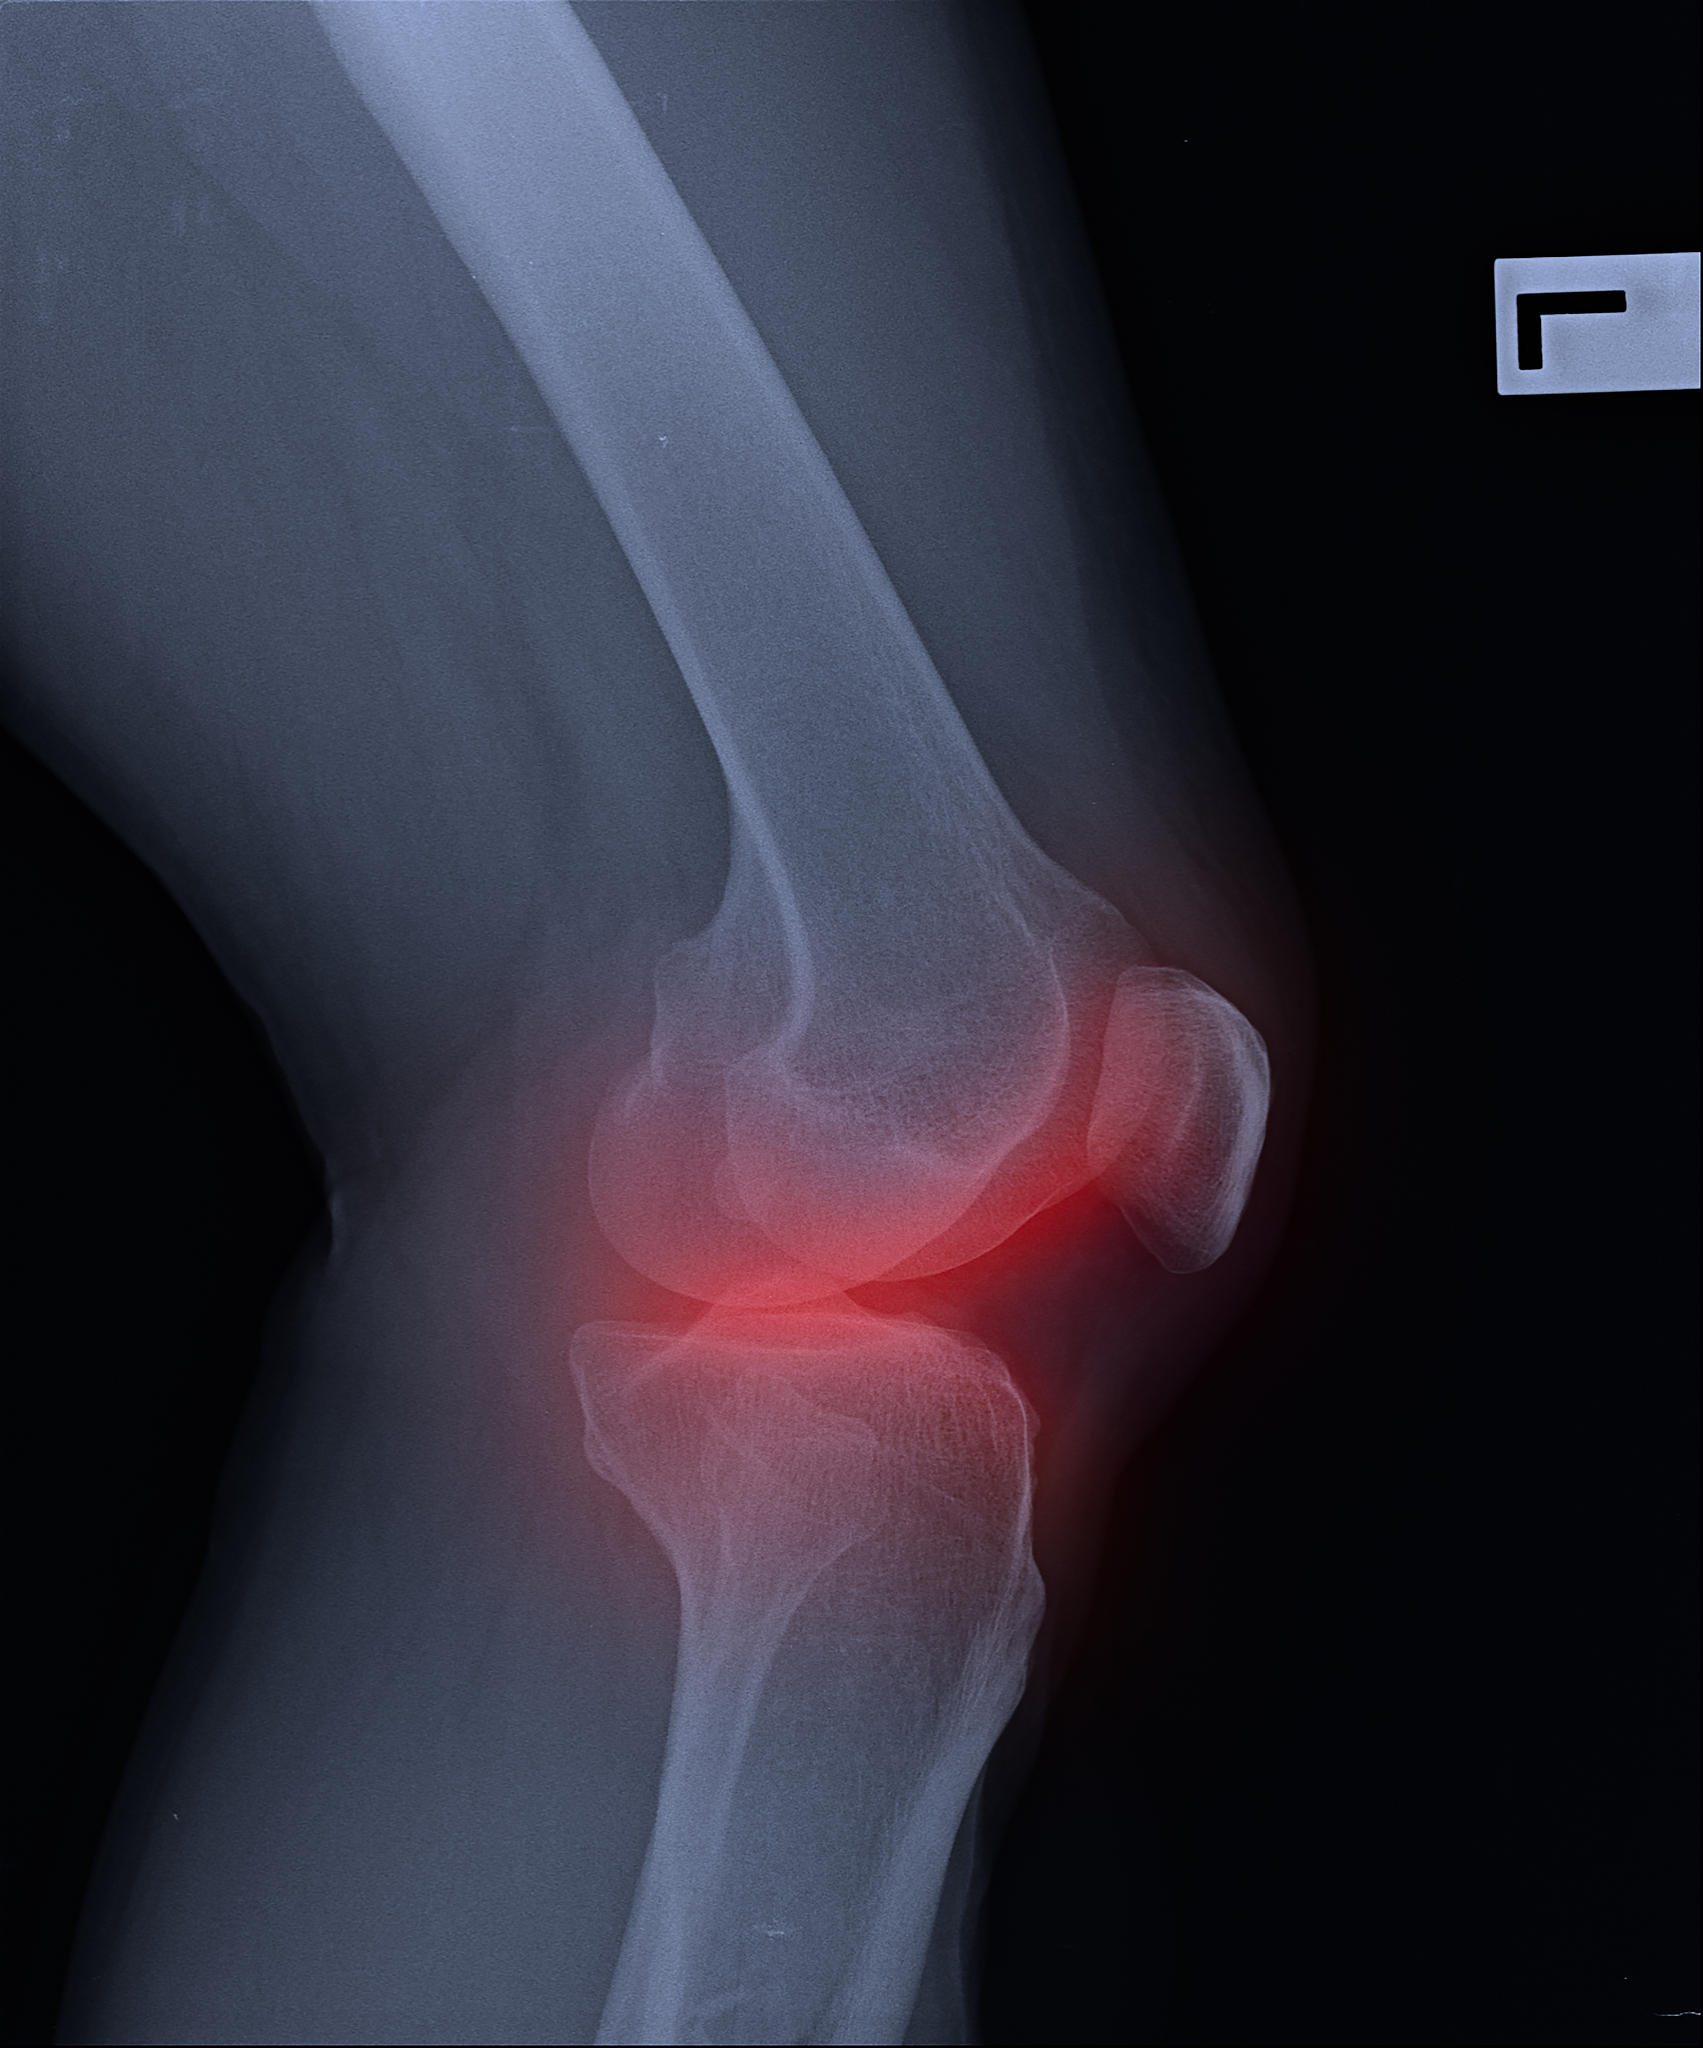

膝关节骨性关节炎是一种慢性炎症性疾病,主要影响膝关节。它通常是由于关节软骨的退化和破坏引起的,导致关节变形、疼痛和功能障碍。

膝关节骨性关节炎的症状包括膝关节疼痛、僵硬、肿胀和活动受限。疼痛通常会在活动后加重,而休息和睡眠时会减轻。随着疾病的进展,膝关节可能会变形,导致腿部畸形和行走困难。

膝关节骨性关节炎的风险因素包括年龄、肥胖、关节受伤、家族遗传、肌肉无力和关节过度使用。诊断通常通过病史、体格检查和影像学检查(如X射线或MRI)进行。